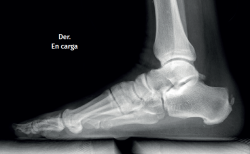

Plain radiography

The dorsoplantar and sagittal views of both feet under loading conditions are indicated, together with the posteroanterior view of the ankles under loading conditions.

Figure 3. Plain radiography, Sagittal view with weight-bearing. Moderate calcifications in the insertion of the Achilles tendon with intratendinous enthesophyte. Morphological alterations of the posterior tuberosity of the calcaneus.

Plain radiography under loading conditions is the essential initial diagnostic tool(20). It allows us to assess alignments and dysmetria, to measure angles, to determine the morphology of the calcaneus and its posterior tuberosity, to characterise bone exostosis and increments in thickness of the retrocalcaneal soft tissues, and to plan surgical procedures (Figure 3).